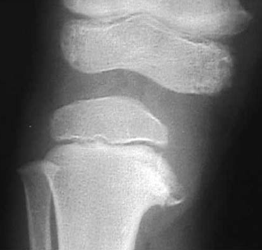

défaut de croissance du tibia interne supérieur: bilatérale 60%

- Lesion métaphysaire tibiale interne

-Angle entre physe et la diaphyse